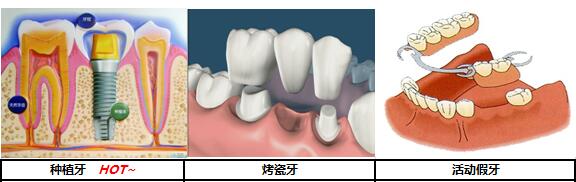

传统的镶牙方式有活动假牙和固定假牙两种方式,活动的假牙因为有个牙托含在嘴里,经常让人很不舒服。固定的假牙舒适度比活动假牙的好,可是需要磨除旁边健康的牙齿较多,造成了缺失一颗牙齿就必须要做三颗假牙的后果。

固定假牙多为“烤瓷冠”,它是将缺牙相邻的两颗健康牙齿磨小,搭起一座“烤瓷桥”来支撑假牙,“桥”中间是一颗或多颗完整的假牙,“桥”两头的假牙形状相当于两颗被磨小的牙的“帽子”,这种方法需要把原来健康的牙齿人为地磨小。

种植牙,是把种植体通过一个小手术植入到牙槽骨中,然后在上面安装牙冠的修复方式。由于人工牙相当于我们自然牙的牙根,可承受正常的咀嚼力量,功能和美观上几乎和自然牙一样,被称为人类的第三副牙齿。>>>种一颗牙要多少钱?<<<